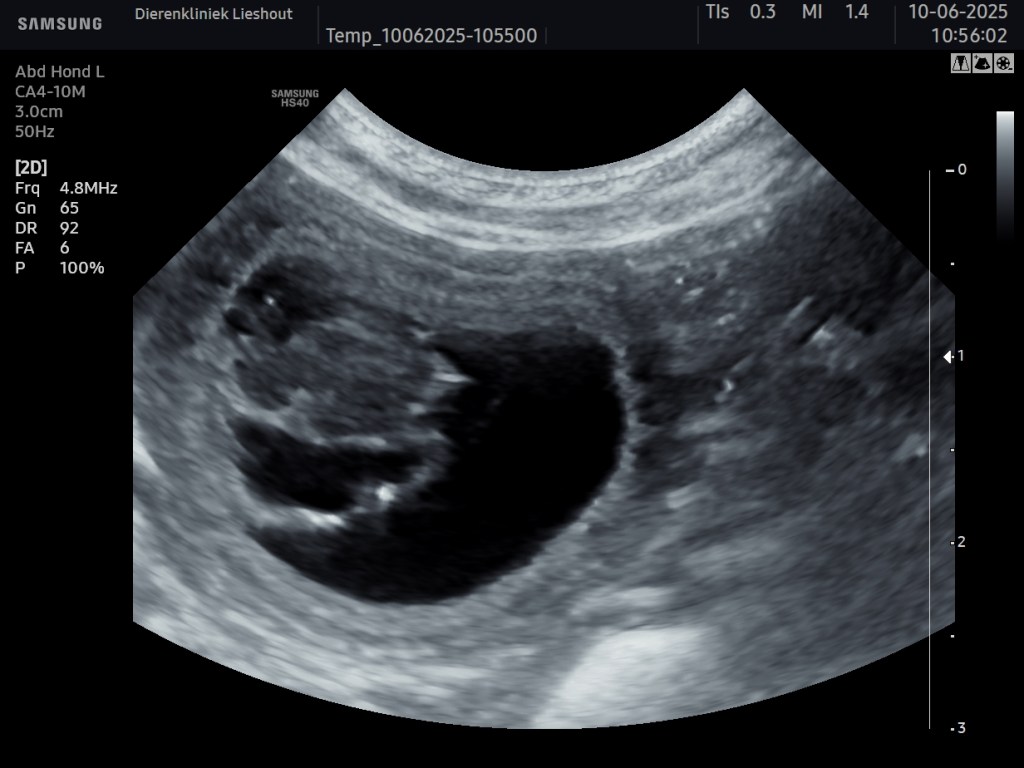

Dinsdag 10-juni is er een echo gemaakt van Molly en ja… ook zij is drachtig !!

Hoeveel precies? dat weten we over 3 a 4 weken!

Echo van Molly waar we meer dan 3 pups gezien hebben.